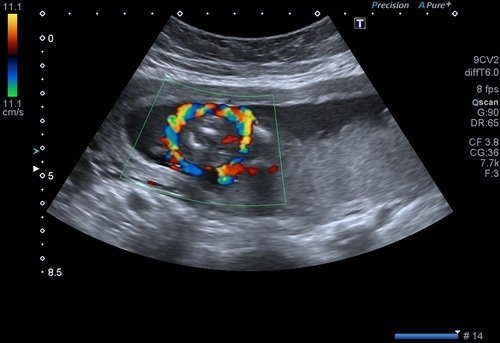

Obstetrik renkli doppler ultrason incelemesinde rahmi besleyen ana damarlar, plasentadan bebeğe doğru giden kordon damarları, bebeğin beyin ve karın bölgesindeki damarlar incelenir.